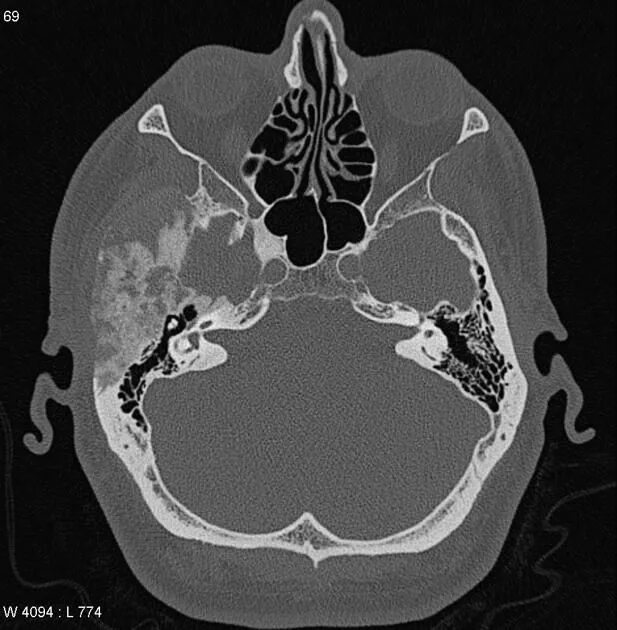

Череп на кт